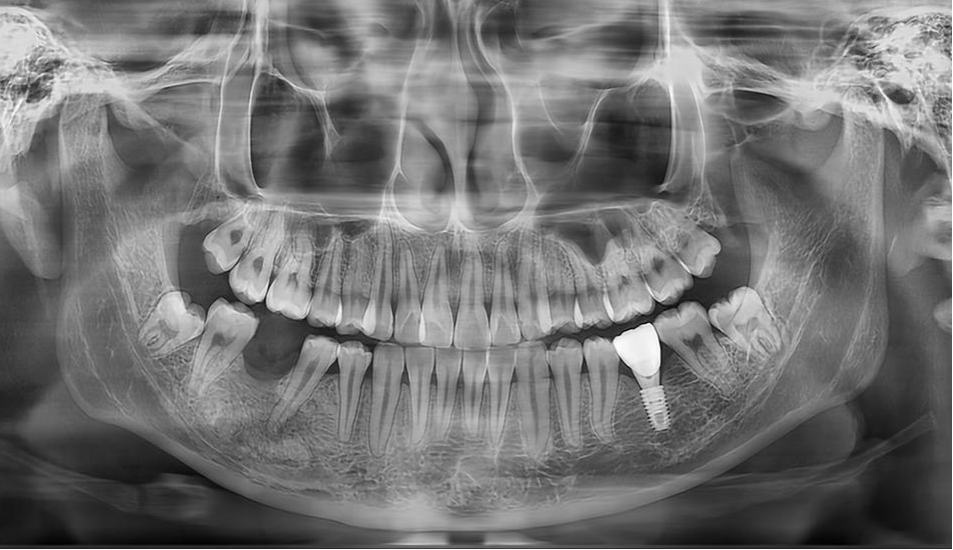

令人欣慰的是,莉莉术后恢复良好,没有出现下唇麻木等神经损伤症状。经过一年的定期随访复查,最新的X光片显示她下颌骨缺损区域已经实现了良好的骨质再生,为后续的种植牙修复奠定了坚实基础。